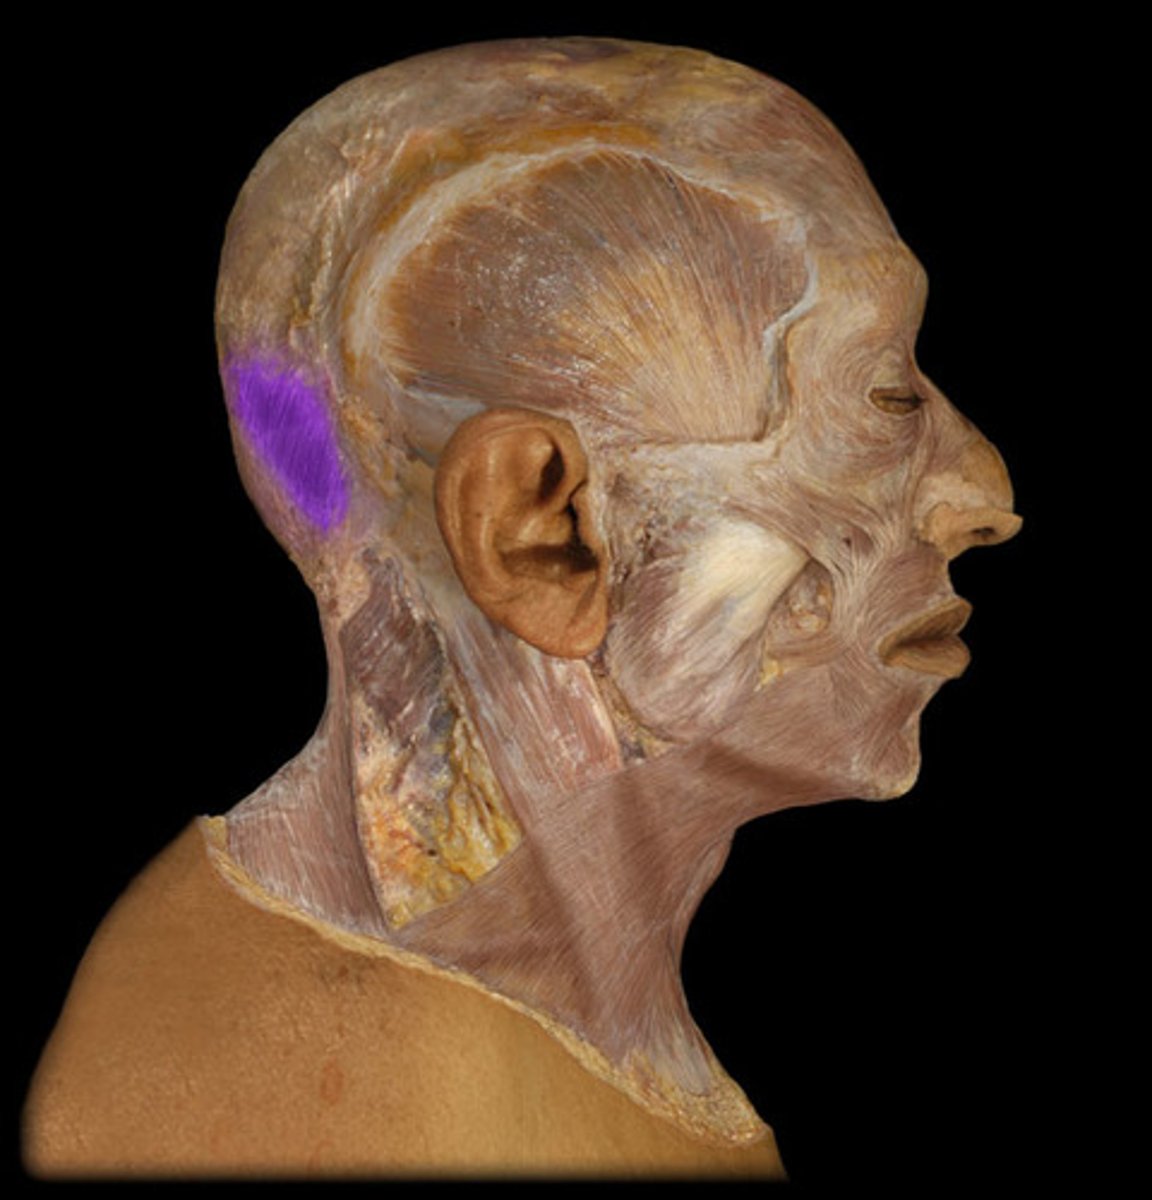

Occipital belly of occipitofrontalis